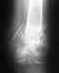

Какими бы большими буквами Вы не писали, что "ЗНАЕТЕ", что нога короче, это не заменит профессионально выполненного измерения относительной и абсолютной длины конечностей и их сегментов. Еще надежнее сделать снимок бедер со смежными суставами с рентгеноконтрастной линейкой.